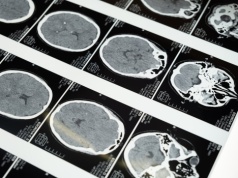

Niemieccy badacze pokazali, że głęboko zamrożona tkanka mózgowa myszy może po rozmrożeniu odzyskać część swoich funkcji. Dla kriobiologii to oczywisty przełom, ale i tak do wizji "wybudzania" zamrożonych orgniazmów jest jeszcze długa droga.